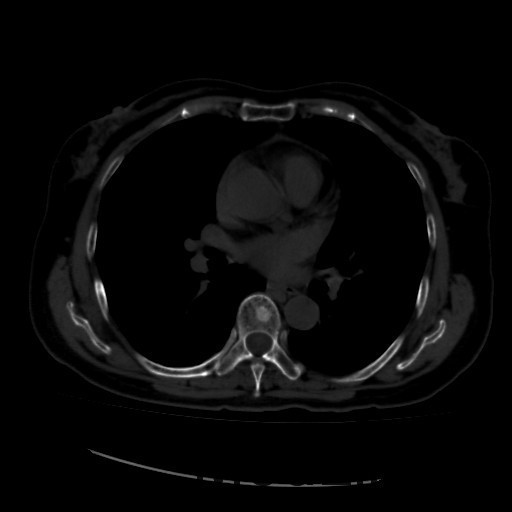

诊断:甲状腺恶性肿瘤(术后);手术后甲状腺功能减退。 治疗:入院时甲状腺球蛋白>455pmol/L,甲状腺素2.793uIU/ml,根据病情于2014-6-3予大剂量碘-131 100mCi清甲治疗;2014年6月全身碘扫示:全身多发异常摄碘组织,考虑甲状腺癌术后双侧甲状腺组织及锥状叶残留并全身多发骨转移。2014年9月胸部CT示:1、双肺多发转移瘤,并胸骨转移;胸1、8、10、腰1椎体内多发结节灶,考虑转移瘤可能性大。2、右肺中叶内侧段、双肺下叶散在慢性炎症。2014年12月全身碘扫:1.全身多处异常摄碘组织,考虑多发骨转移瘤。又于2014年12月复查甲状腺球蛋白抗体90.400U/mL,促甲状腺素6.914uIU/ml。遂于2014-12-22口服250mCi大剂量放射性碘-131。治疗后全身碘扫复查结果提示:2.左肺下叶摄碘组织,不排除转移瘤,建议进一步检查。与2014.6.6检查相比,颈部甲状腺部位放射性浓集灶消失,余病灶放射性浓集程度较前稍降低。

患者又于2015年10月胸部CT复查,结果提示:1、甲癌术后改变;双肺多发转移瘤,大部分病灶较前缩小,左肺下叶病灶较前增多,部分较前增大;胸骨转移;胸1、8、10、腰1椎体内多发结节灶,基本同前,考虑转移瘤可能性大。2、右肺中叶内侧段、左肺上叶舌段及双肺下叶散在慢性炎症。